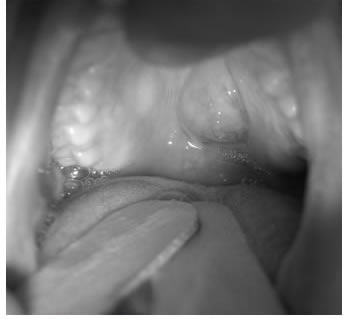

En muchas ocasiones, el tumor primario es evidente al examen físico, con posibilidades de realizar biopsias por incisión bajo anestesia local y evitar retrasos en la atención y más cicatrices en áreas externas, como ocurre con los tumores de lengua o la orofaringe (figura 2).